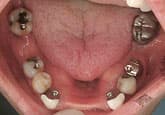

MJさん(20歳・女性)

初診時:左上の歯肉が痛い

初診時

3週間後

さらに正しいはみがき

を行って3週間後

ここまで患者さんが丁寧に歯をみがいただけです。

歯科医と衛生士は何もしていません。

さらに3週間後

歯石除去

歯石が見えてきたので、歯石を除去しました。

健康な歯肉に回復しました。